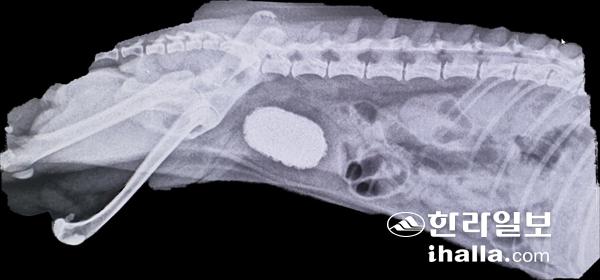

지난달이었다. '빗짱'이라는 이름의 강아지였는데 산책할 때 소변을 시원하게 해결하지 못하고 자꾸 찔끔찔끔 하고 피가 섞인 오줌(혈뇨)이 발견돼 병원을 찾았다. 나이는 5세, 중성화가 되지 않은 암컷 치와와였다. 복부촉진과 방사선 촬영, 초음파 검사를 통해 지름3㎝ 가량의 방광결석을 확인했고 방광의 대부분이 결석으로 채워져서 방광파열로 이어질 수 있는 상태였다. 이 결석은 외과적 수술을 통해 제거했고 , 빗짱이는 몇일의 회복시간을 가진 뒤 건강하게 퇴원했다. 빗짱이의 경우 결석의 종류는 스트루바이트라는 것이었고 이 결석은 대부분 요소분리세균에 의한 감염으로 발생하는데 알칼리소변, 식이요인, 유전적 소인이 관련돼 있다. 대체로 심한 통증을 동반하지 않아 결석이 방광을 거의 폐쇄할 정도로 커질 때 까지 보호자가 모르는 경우가 대부분이다.

빗짱이의 방사선 사진.